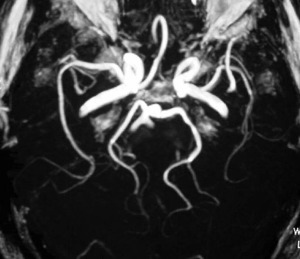

This scan shows tissues, muscle, cartilage, bone marrow, ligaments, tendons and blood vessels inside the body. A MRI scan can also give your doctor important information about the heart, if needed.